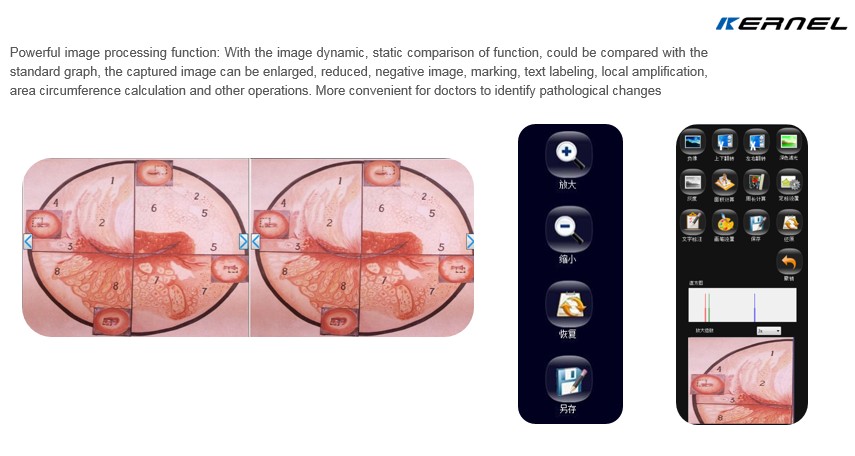

About software

All of our colposcope come with Free Multifunctional software

>>>>Capture Images,Take Videos,Acetic Acid test timing ,Case report,175 Clinical disgnostic data bases comparison